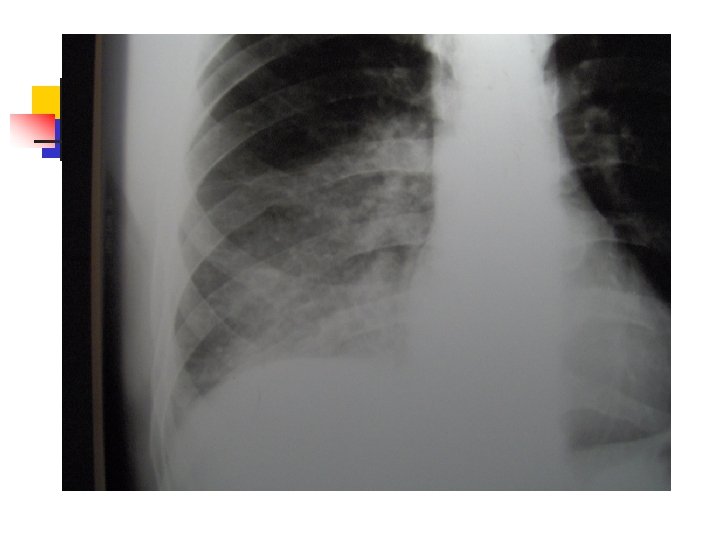

Aproximación diagnóstica: Radiología n n n 250 ml son necesarios para provocar alteraciones radiológicas. Primer signo: Borramiento del SCD Damoisseau. Desviación de estructuras. Derrame tabicado.